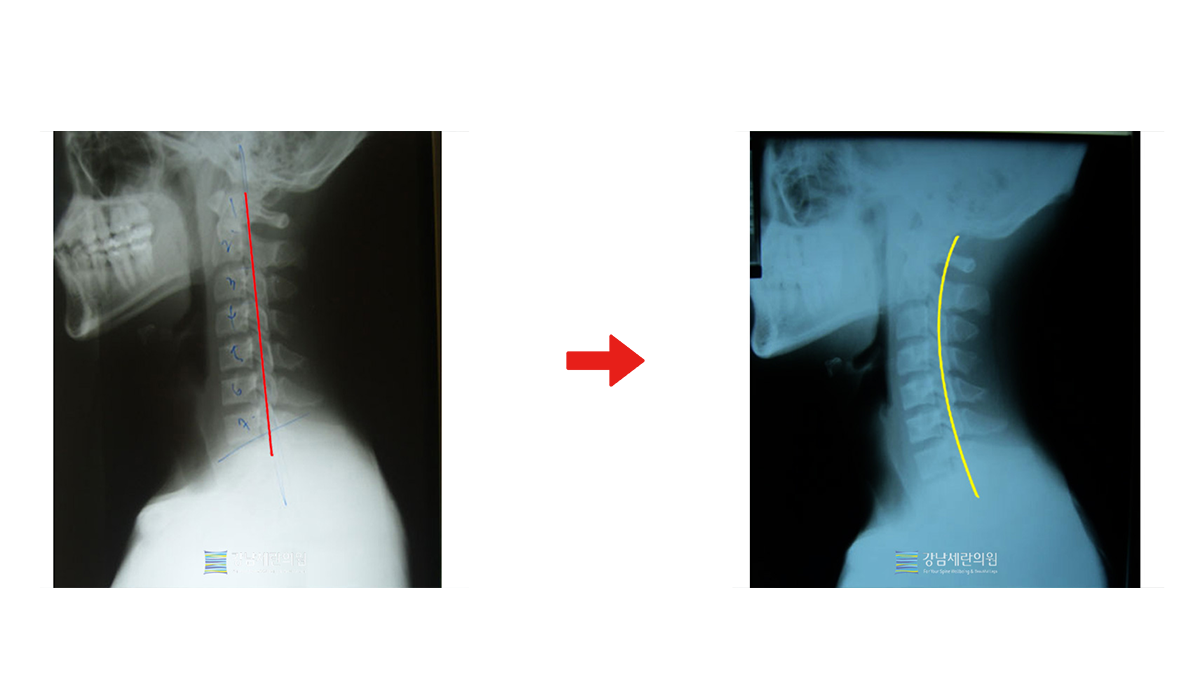

#일자목

일자목 치료 전 ▶ 일자목 30회(3개월) 치료 후